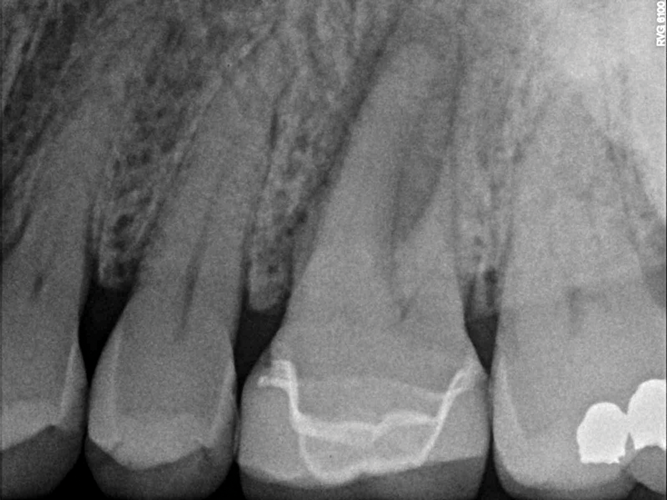

Fig 2. This penicillin-allergic patient presented with facial swelling secondary to pulpal necrosis with acute apical abscess on tooth No. 14 (Fig 2 and Fig 3). The swelling was consistent with cellulitis, thus systemic antibiotics were indicated in addition to definitive treatment by nonsurgical root canal therapy (Fig 4). Prior to 2019, clindamycin would have been the drug of choice, but newer guidelines warranted first-line use of cephalexin instead.10 Treatment in this case was initiated concurrently with antibiotic prescription and completed over two visits with the use of interappointment, intracanal calcium hydroxide. The infection resolved after treatment without complication.

Fig 3. This penicillin-allergic patient presented with facial swelling secondary to pulpal necrosis with acute apical abscess on tooth No. 14 (Fig 2 and Fig 3). The swelling was consistent with cellulitis, thus systemic antibiotics were indicated in addition to definitive treatment by nonsurgical root canal therapy (Fig 4). Prior to 2019, clindamycin would have been the drug of choice, but newer guidelines warranted first-line use of cephalexin instead.10 Treatment in this case was initiated concurrently with antibiotic prescription and completed over two visits with the use of interappointment, intracanal calcium hydroxide. The infection resolved after treatment without complication.

Fig 4. This penicillin-allergic patient presented with facial swelling secondary to pulpal necrosis with acute apical abscess on tooth No. 14 (Fig 2 and Fig 3). The swelling was consistent with cellulitis, thus systemic antibiotics were indicated in addition to definitive treatment by nonsurgical root canal therapy (Fig 4). Prior to 2019, clindamycin would have been the drug of choice, but newer guidelines warranted first-line use of cephalexin instead.10 Treatment in this case was initiated concurrently with antibiotic prescription and completed over two visits with the use of interappointment, intracanal calcium hydroxide. The infection resolved after treatment without complication.